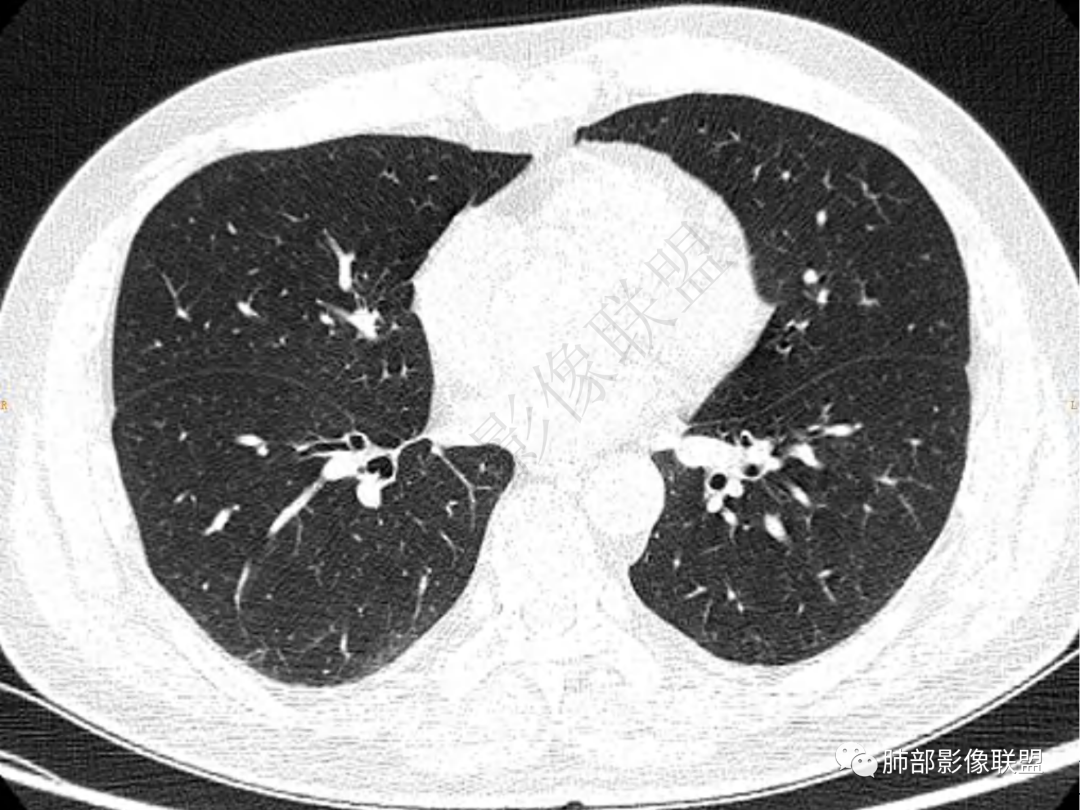

3.周边较大范围磨玻璃影,边界相当模糊,小叶增厚明显。注意叶裂另一侧、左肺舌段亦可见磨玻璃影及增厚的小叶间隔。未见明确卫星病灶。

2.周围磨玻璃影边界不清缺乏限制,甚至“激惹”到相邻肺叶,也许提示较明显的炎性水肿。

肺脓肿:边界模糊不清,或者块影为类圆形,无明显分叶,边缘平直为主,刀切征——炎性特点三、病灶周围特点:肺脓肿:病灶非远端有片状GGO——炎性特点四、近端支气管阻塞:肺脓肿:常有引流支气管伴管壁增厚或者支气管沿洞壁走行。五:坏死壁:肺脓肿:大多壁厚,少数壁薄,没有壁结节,内壁清楚光整——炎性特点